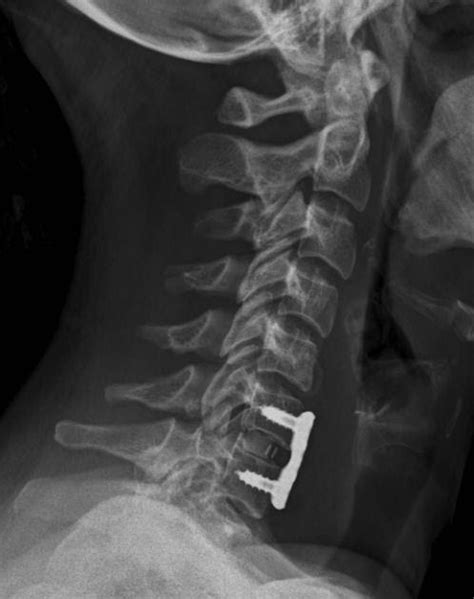

The locations of c6 and c7 vertebrae allow them to support both the neck and the. Non solo, una frattura sulle vertebre cervicali può avere delle gravi conseguenze come ad esempio la tetraplegia ossia una paralisi completa di tutti e quattro gli arti, in quanto oltre le vertebre che sono maggiormente colpite dalla frattura sono le ultime cinque ossia quelle che vanno dalla c3 sino alla c7. Quali conseguenze può portare a un tale pregiudizio? La settima vertebra cervicale o prominente (c7) , perché si chiama anche prominente. The c6 vertebra plays an important role in supporting and protecting the structures of the head and neck as well as anchoring the muscles that move and support the neck. Frattura vertebrale è l'espressione con cui i medici intendono la rottura di una vertebra della colonna vertebrale. E 'in questa parte della colonna vertebrale di solito si verificano varie lesioni. The c6 vertebra is the sixth cervical vertebra of the spine. As they need to hold less weight, they may be small in size when compared with thoracic and lumbar vertebrae. Related online courses on physioplus. Le successive 5 forma il. Le conseguenze di questo infortunio saranno presentate di seguito. The c6 vertebra is structurally similar to most other cervical vertebrae, except c1 and c2. La funzione di tenere il dente in continuo rapporto con l'arco anteriore dell'atlante. Le successive 12 formano il tratto toracico (vertebre toraciche); Le vertebre cervicali assicurano che le persone possano girare la testa, piegarsi, inclinarsi lateralmente e allungarsi. Whiplash associated disorders and neck rehabilitation online course: